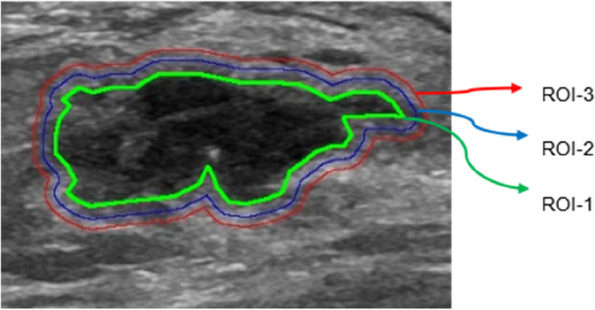

The BC lesions located in US B-mode images were manually delineated along the tumor edge by a radiologist (with 3 years of experience in breast imaging) as the region of interest (ROI-1). Another radiologist (with 10 years of experience in breast imaging) examined all of the ROIs. If the readings were discordant, agreement was arrived at by a joint review of the images. Neither physician was aware of the patient’s gBRCA mutation status. When there were multiple lesions in the image, the largest lesion was selected as the target lesion. Based on other previous imaging studies of the peri-tumor area of breast cancer [15, 19, 20], we decided to externally expand the peri-tumor area to 3 mm and 5 mm. The Opencv package of the Python program was used to semi-automatically segment the peritumoral area (ROI-2 and ROI-3, including the peritumoral parenchyma representing 3 mm and 5 mm extensions outward, respectively) (Fig. 1).

Fig. 1.

The regions of interest. ROI = region of interest; ROI-1 = intratumoral area; ROI-2 = 3 mm peritumoral region; ROI-3 = 5 mm peritumoral region